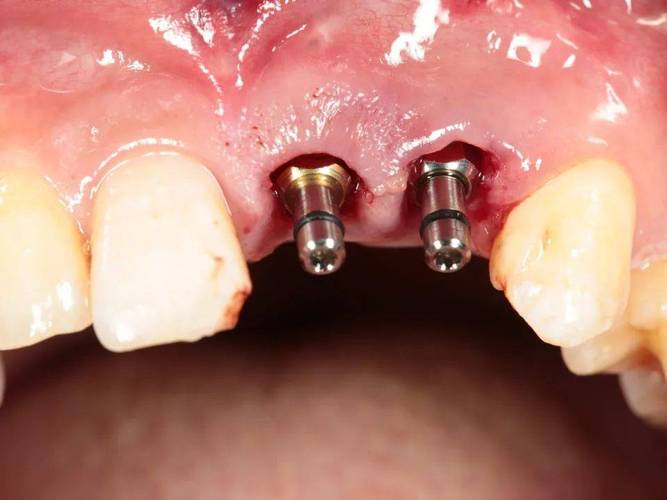

种植手术:

- 常规流程:切开牙龈、暴露牙槽骨、备洞、植入种植体、缝合牙龈。

- 手术时间根据种植数量和复杂程度而定(单颗通常30-60分钟)。

- 数字化导板辅助下手术更精准微创。